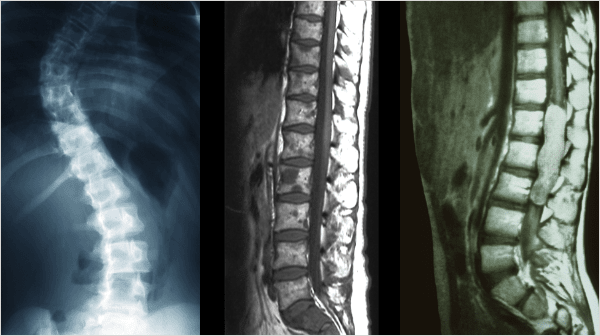

척추측만증,후만증,전만증

추의 만곡이 소실되어 척추가 왼쪽 혹은 오른쪽으로 휘어지는 증상을 척추측만증,

허리뼈가 아무런 굴곡없이 일자로 꼿꼿한 허리를 후만증, 앞쪽으로 휘어지는 증상을 전만증 이라고 합니다.